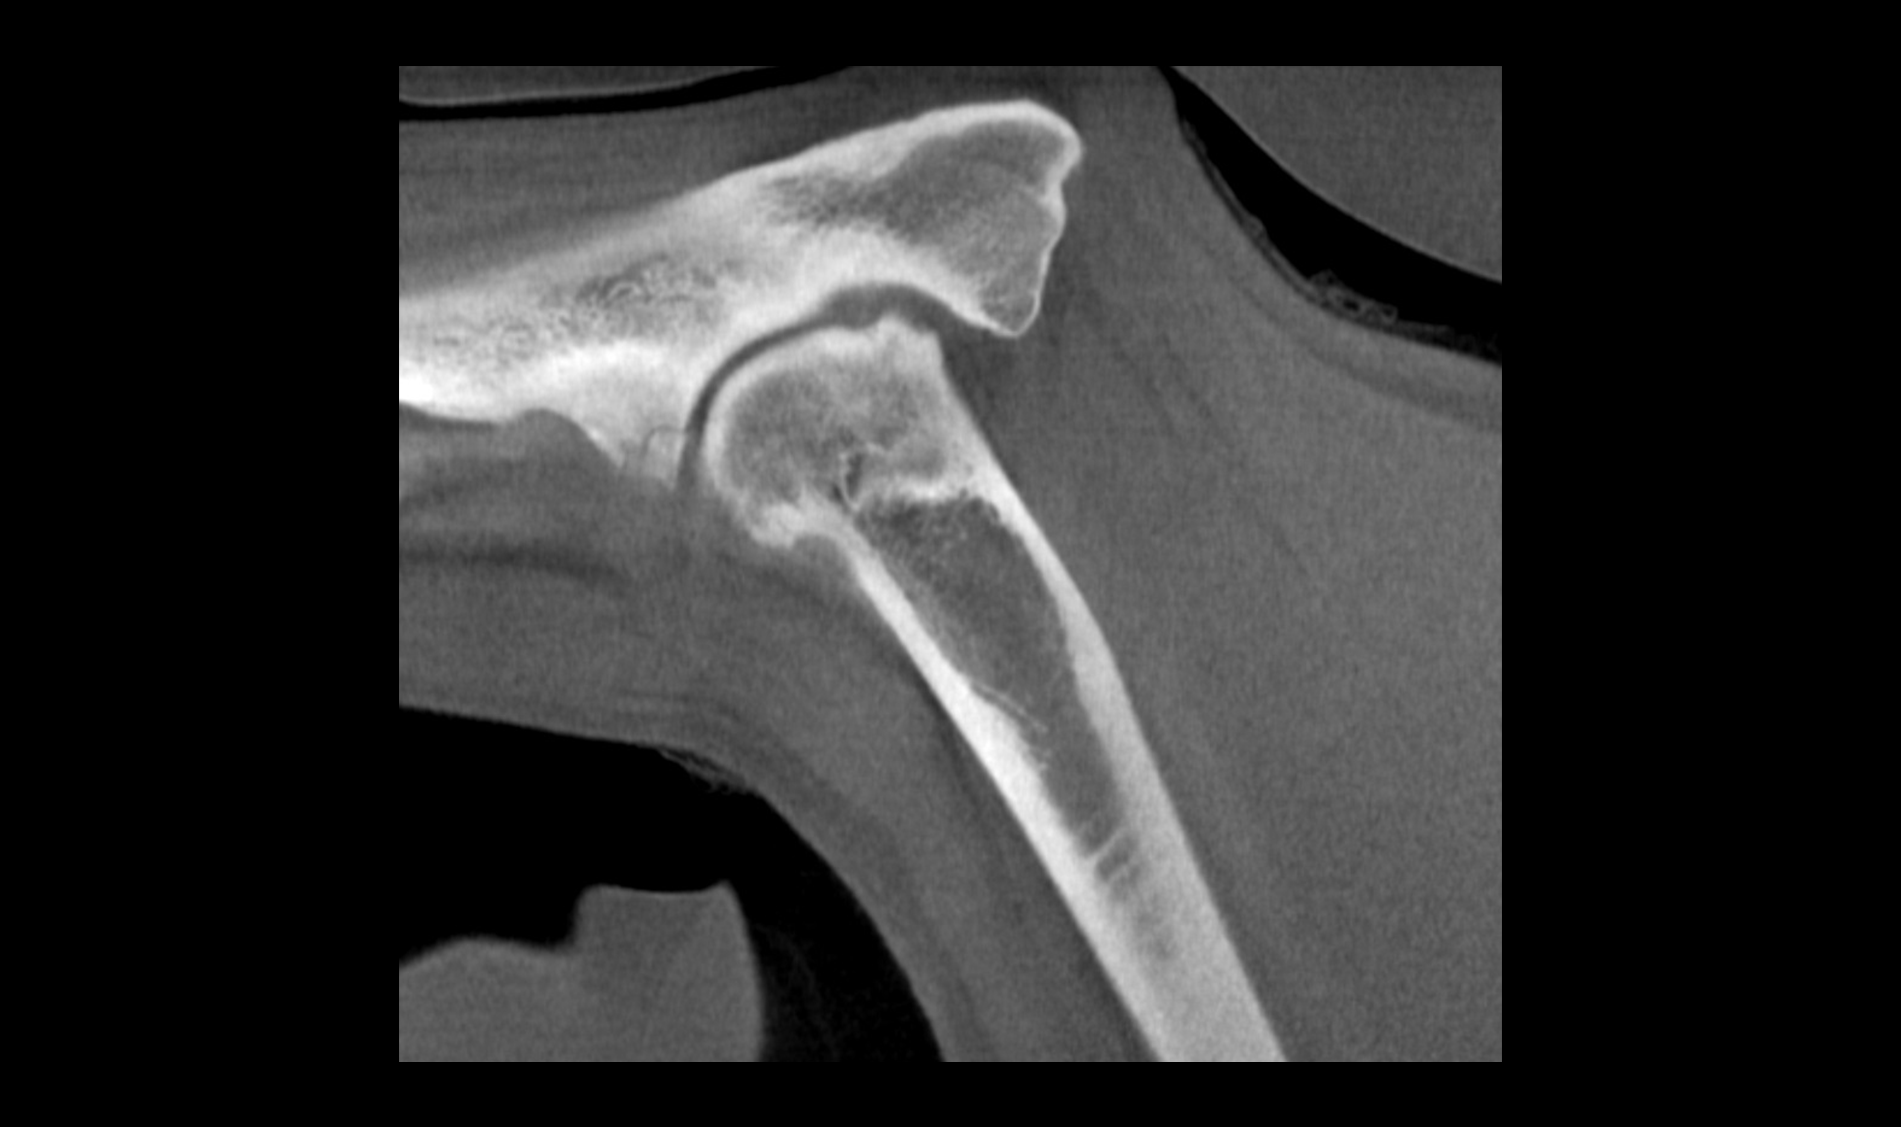

HDVI and HRCT

SPATIAL RESOLUTION

Outstanding image quality in hard tissues.

Human CT Scanner Innovation

Imaginalis innovative vision has led to a new milestone: the development of a human CT scanner that promises to revolutionize the medical sector, particularly in orthopedic applications.

Precision Diagnosis & Treatment

Our scanner introduces advanced technology that offers high-resolution images and greater imaging flexibility, allowing for more precise diagnosis and optimized treatment planning.